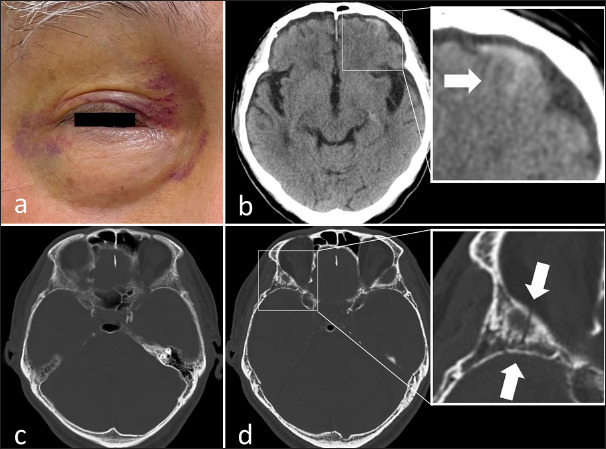

Case description: An 85-year-old male with a 30-year history of insulin-treated type 2 diabetes presented with raccoon sign one morning, without additional symptoms. A comprehensive physical examination, including a detailed head assessment, revealed no abnormalities. However, computed tomography (CT) imaging identified a minor subarachnoid hemorrhage, and high-resolution CT imaging (1-mm bone slice thickness) detected a thin orbital roof fracture, confirming a traumatic contrecoup injury. This finding rendered the differential diagnosis for nontraumatic causes irrelevant. The patient's longstanding diabetes was considered a relevant factor in the development of the raccoon sign.

Conclusion: In older adult patients presenting with raccoon sign but lacking overt symptoms, obtaining a thorough history of head trauma and diabetes is essential, even in cases of minor injury without visible external signs. High-resolution thin-slice bone CT imaging is vital for detecting subtle orbital roof fractures, which may otherwise go unnoticed. Early identification facilitates accurate diagnosis and prevents unnecessary evaluations for nontraumatic causes.